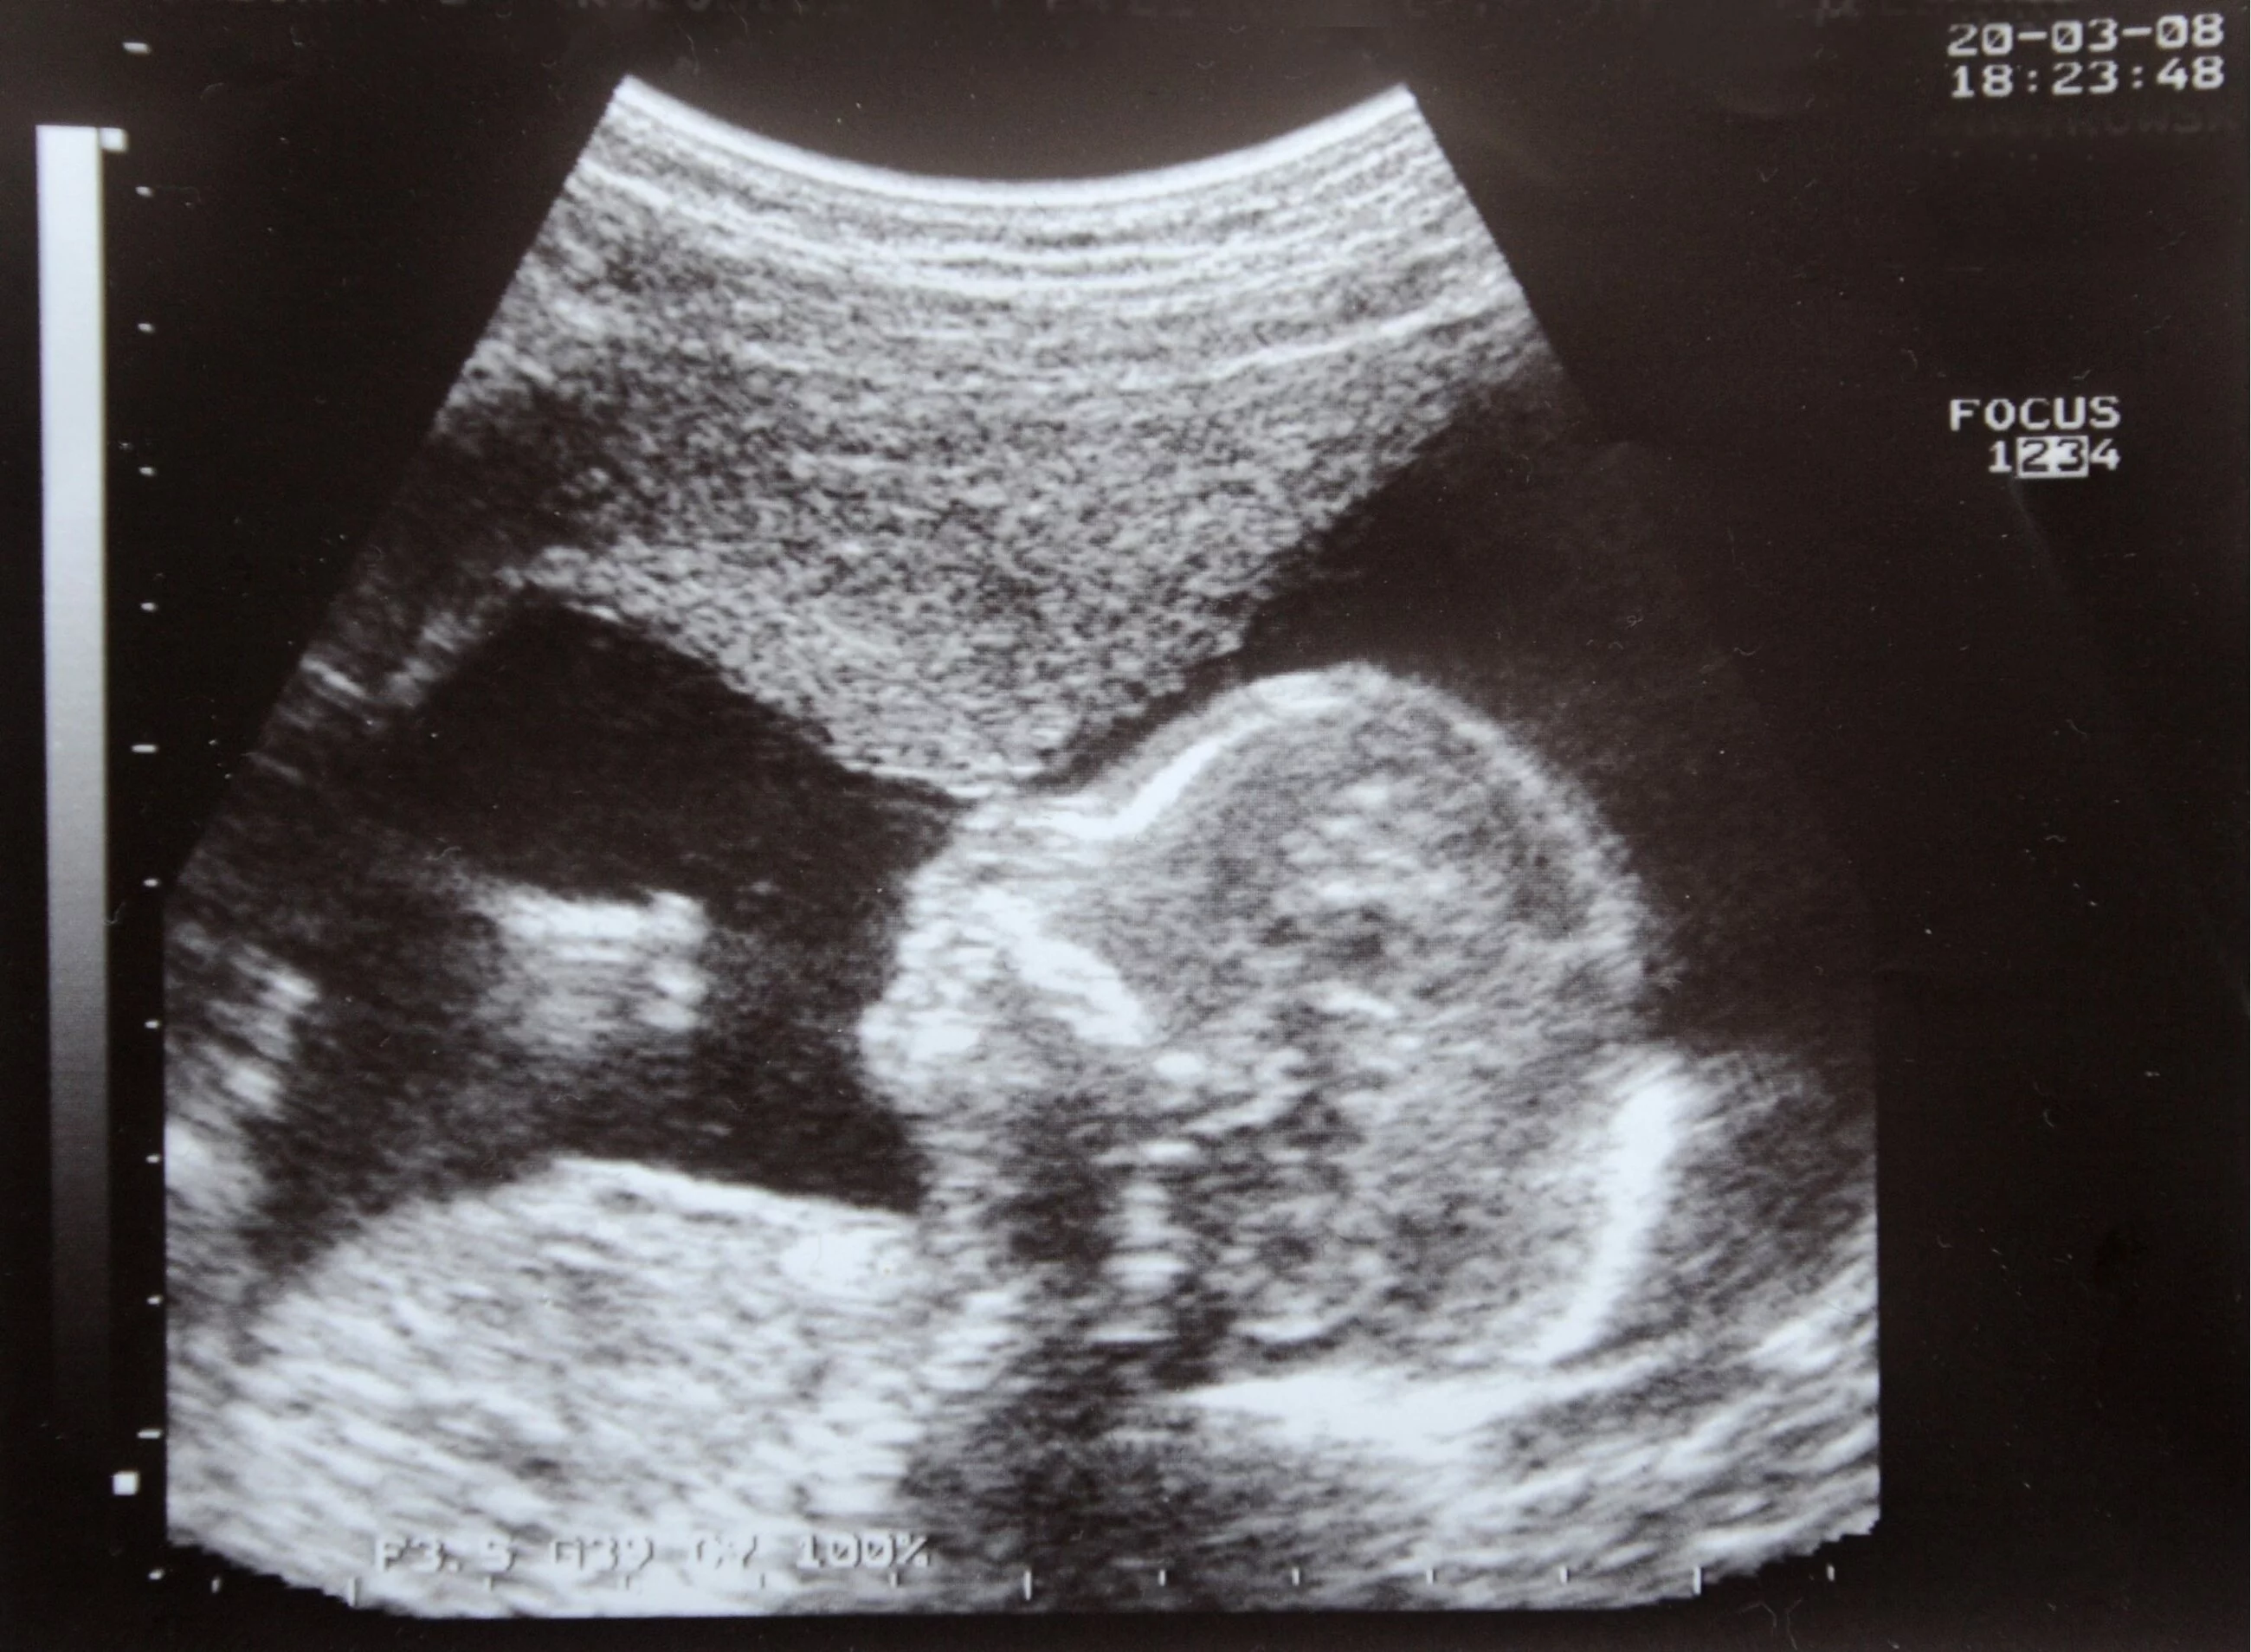

Po 12-godzinnej debacie większość senatorów poparła liberalizację przepisów. Ustawa została wcześniej uchwalona przez Izbę Deputowanych, a poparcie dla niej wyrażał prezydent Argentyny Alberto Fernández. Nowe prawo umożliwi legalne przerywanie ciąży do 14 tygodnia.

Do tej pory w Argentynie aborcja była możliwa jedynie w przypadku zagrożenia życia kobiety lub gwałtu. Przeciwko legalizacji aborcji do 14. tygodnia ciąży stanowczo opowiadał się Kościół. Papież Franciszek, na kilka godzin przed senacką debatą, napisał na Twitterze, że "każdy wyrzutek jest dzieckiem Bożym".